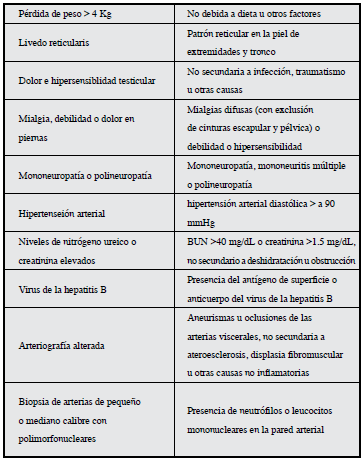

El diagnóstico se apoya en los criterios establecidos en 1990 por el consenso de Chapel Hill y el Colegio Americano de Reumatología (CAR), los cuales sólo han sido validados en adultos (Tabla 2) 7. La presencia de tres criterios o más tiene una sensibilidad de 82.2% y una especificidad de 86.6% 7-9.

Tabla 2 Criterios de clasificación del Colegio Americano de Reumatología para el diagnóstico de poliarteritis nodosa.